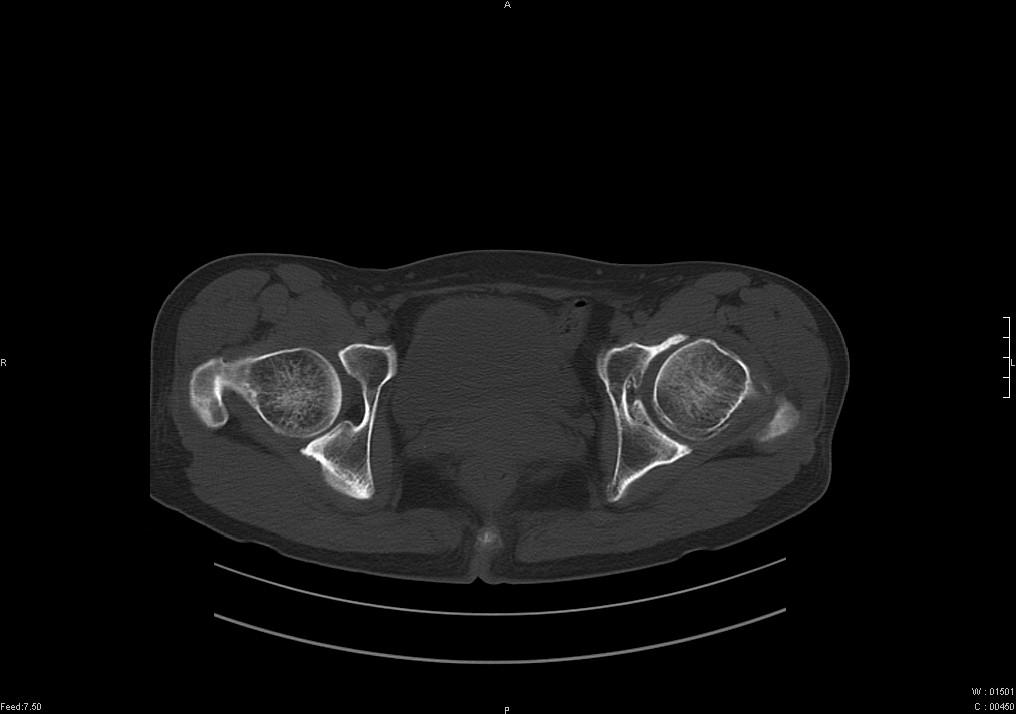

标题: CT19780左髋关节疼痛伴跛行1年,加重1个月。无菌性坏死? [打印本页]

标题: CT19780左髋关节疼痛伴跛行1年,加重1个月。无菌性坏死?

没报年龄,但髋臼有骨质增生, 考虑退行性变,坏死不明显。

左髋关节内内可见关节鼠及滑囊积液.

考虑为滑膜骨软骨瘤病.

滑膜增厚钙化,关节鼠及滑囊积液,髋臼增生。考虑骨性关节病

髋臼平浅,股骨头覆盖率减小,考虑双侧髋关节发育不良伴退行性变。

考虑左髋关节退行性骨关节病;建议必要时行mri检查排除左侧股骨头缺血性坏死。